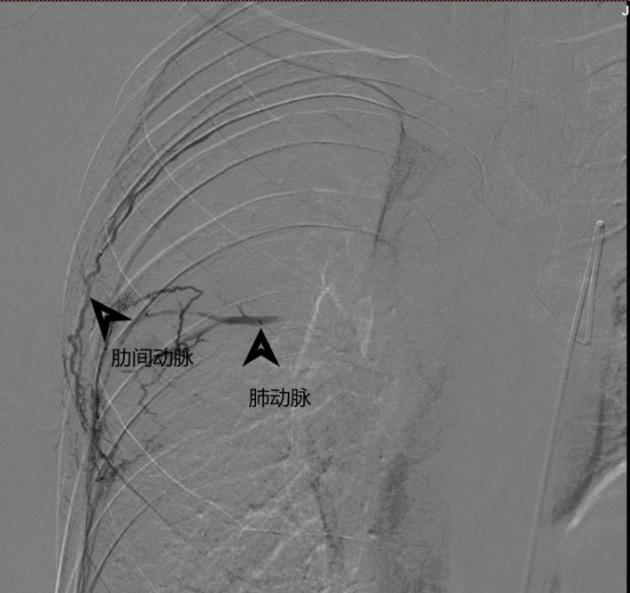

近日,在介入与血管外科张喜成主任医师指导下,程龙副主任医师及顾铖涛医师在DSA下造影找到了病变出血的原因——原来患者存在肋间动脉、支气管动脉肺动脉瘘。于是决定为患者行选择性动脉栓塞术。术中,如下图所示,医生用头发丝样的微导管超选择供血血管,尽可能避开对正常血管的影响后,用栓塞微球将瘘口堵塞住进行精准栓塞,整个手术约1个小时,术后复查咯血症状消失。在医护人员的精心照料下,术后10天,患者顺利康复出院。